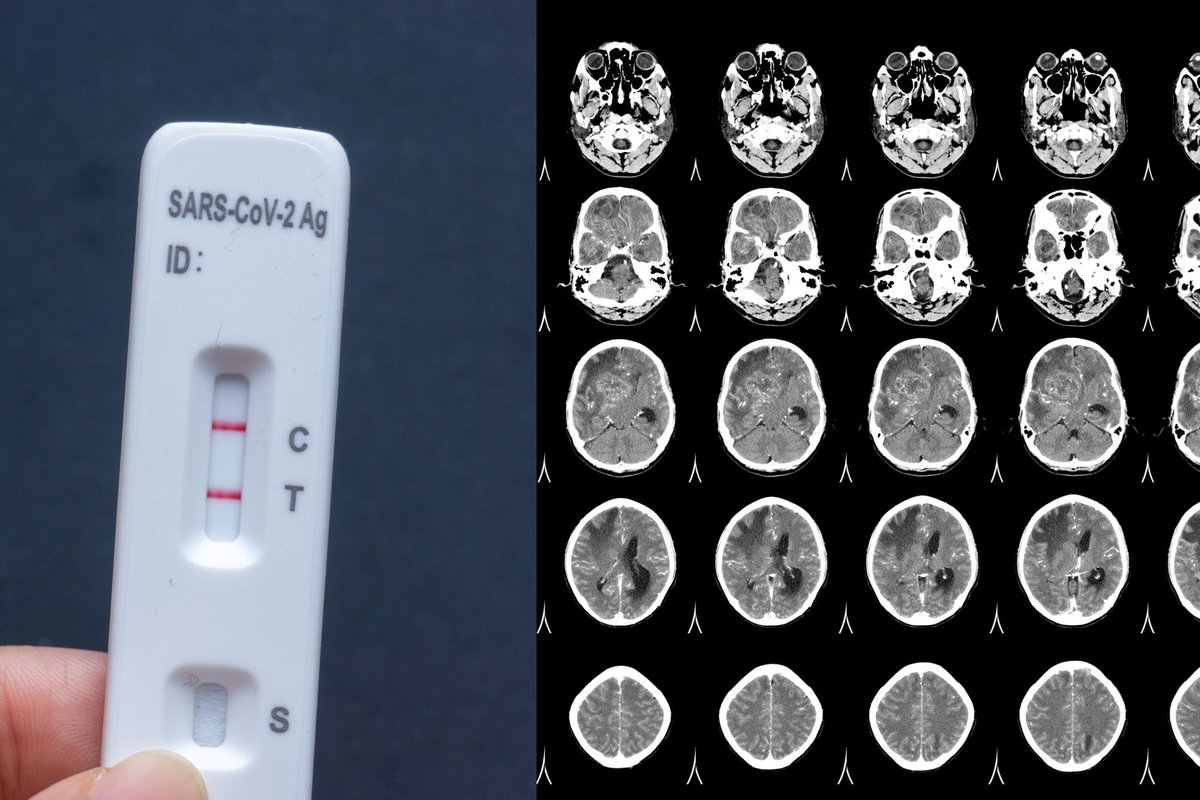

Уровень физической активности также связан с укреплением легких. Регулярное выстраивание дыхания и укрепление дыхательных мышц может помочь улучшить функцию легких и повысить ее резервные возможности. Это имеет большое значение при борьбе с тяжелыми формами инфекции и коронавируса.